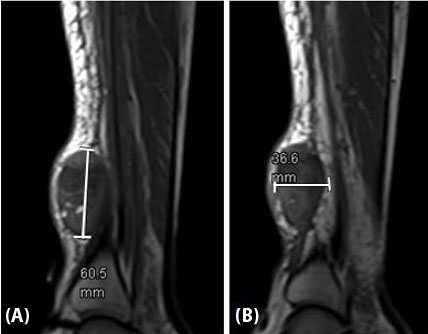

Figure 3: Right lower extremity mass measuring up to 60.5 (A) × 36.6 (B) mm anterior to the distal tibia, staged as cT2 N0 M0 G3.

A 53-year-old African American male presented with an enlarging mass on the right lower leg. Initial X-rays noted a 0.9 cm soft tissue mass that appeared suspicious for intramuscular hematoma on ultrasound. Histology of surgically drained tissue was concerning for malignancy. Magnetic resonance imaging (MRI) showed a 6.1 × 4.8 × 2.6 cm mass anterior to the distal tibia ultimately staged as cT2 N0 M0 G3, resulting in Stage IIIA diagnosis (Figure 3). Immunohistochemistry staining demonstrated UPS given no clear line of differentiation and high Ki67 expression associated with rapid cell proliferation and growth (Figure 4). Genomic testing revealed a FOXP1-TL1X fusion along with mutation of TP53, HRAS, and loss of NF1.